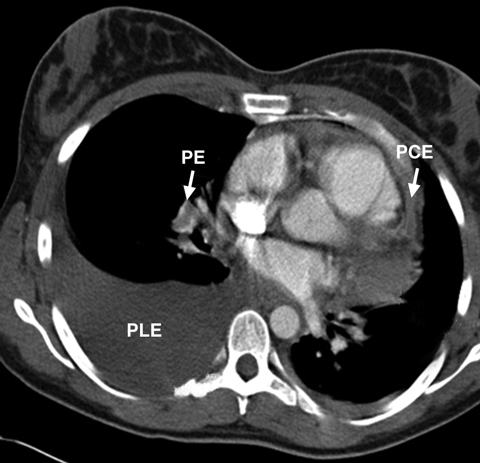

A 25-year-old woman presented with progressively worsening shortness of breath, which was attributed to cardiac tamponade caused by pericardial effusion. Urgent pericardiocentesis revealed haemorrhagic fluid, which continued to accumulate after the procedure. A repeat echocardiogram after pericardiocentesis showed dilatation of the right ventricle and severe pulmonary hypertension. Subsequent computed tomography revealed a massive pulmonary embolism in the right lung (Figure) and multiple small emboli in the left lung, while cytological examination of pericardial and pleural fluid showed adenocarcinomatous cells from a primary lung cancer.

Pericardial effusion and pulmonary embolism usually present in isolation. Their coexistence in this patient — presumably related to the underlying neoplasm — may paradoxically have saved her life, as the raised right ventricular pressure created by the pulmonary emboli delayed the onset of cardiac tamponade.1 Her condition improved initially with chemotherapy and anticoagulation, but she died a year later due to progression of the lung cancer.